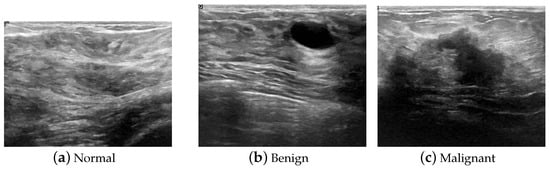

2. Materials